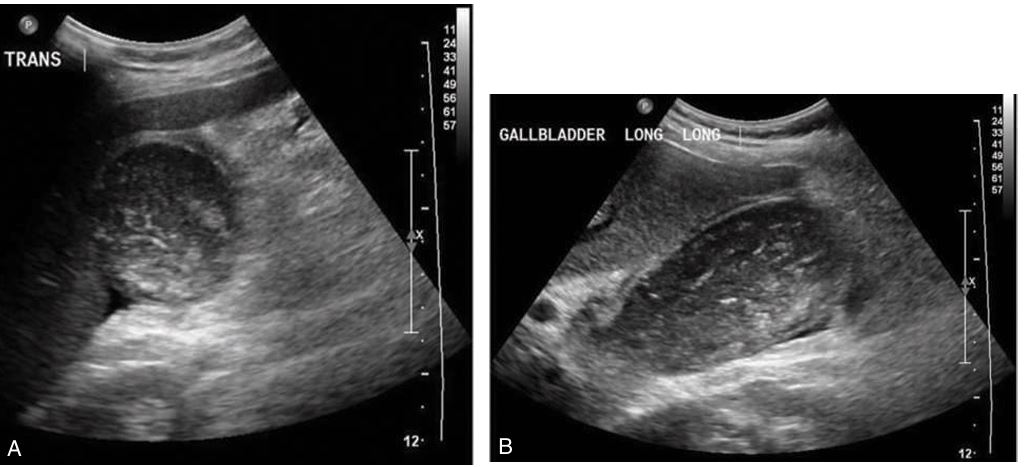

# 1 Pt. c/o RUQ pain, this image looked the same in both supine and LLD positions. Name the pathology

Cholesterolosis showing multiple cholesterol polyps

Adenomyomatosis

artifact: comet tail

Small echogenic Adenoma in GB

the most common pseudotumor of the gallbladder

Cholesterol polyps

Cholesterol polyps

What is the most common benign tumor of the gallbladder?

Cholesterol polyps